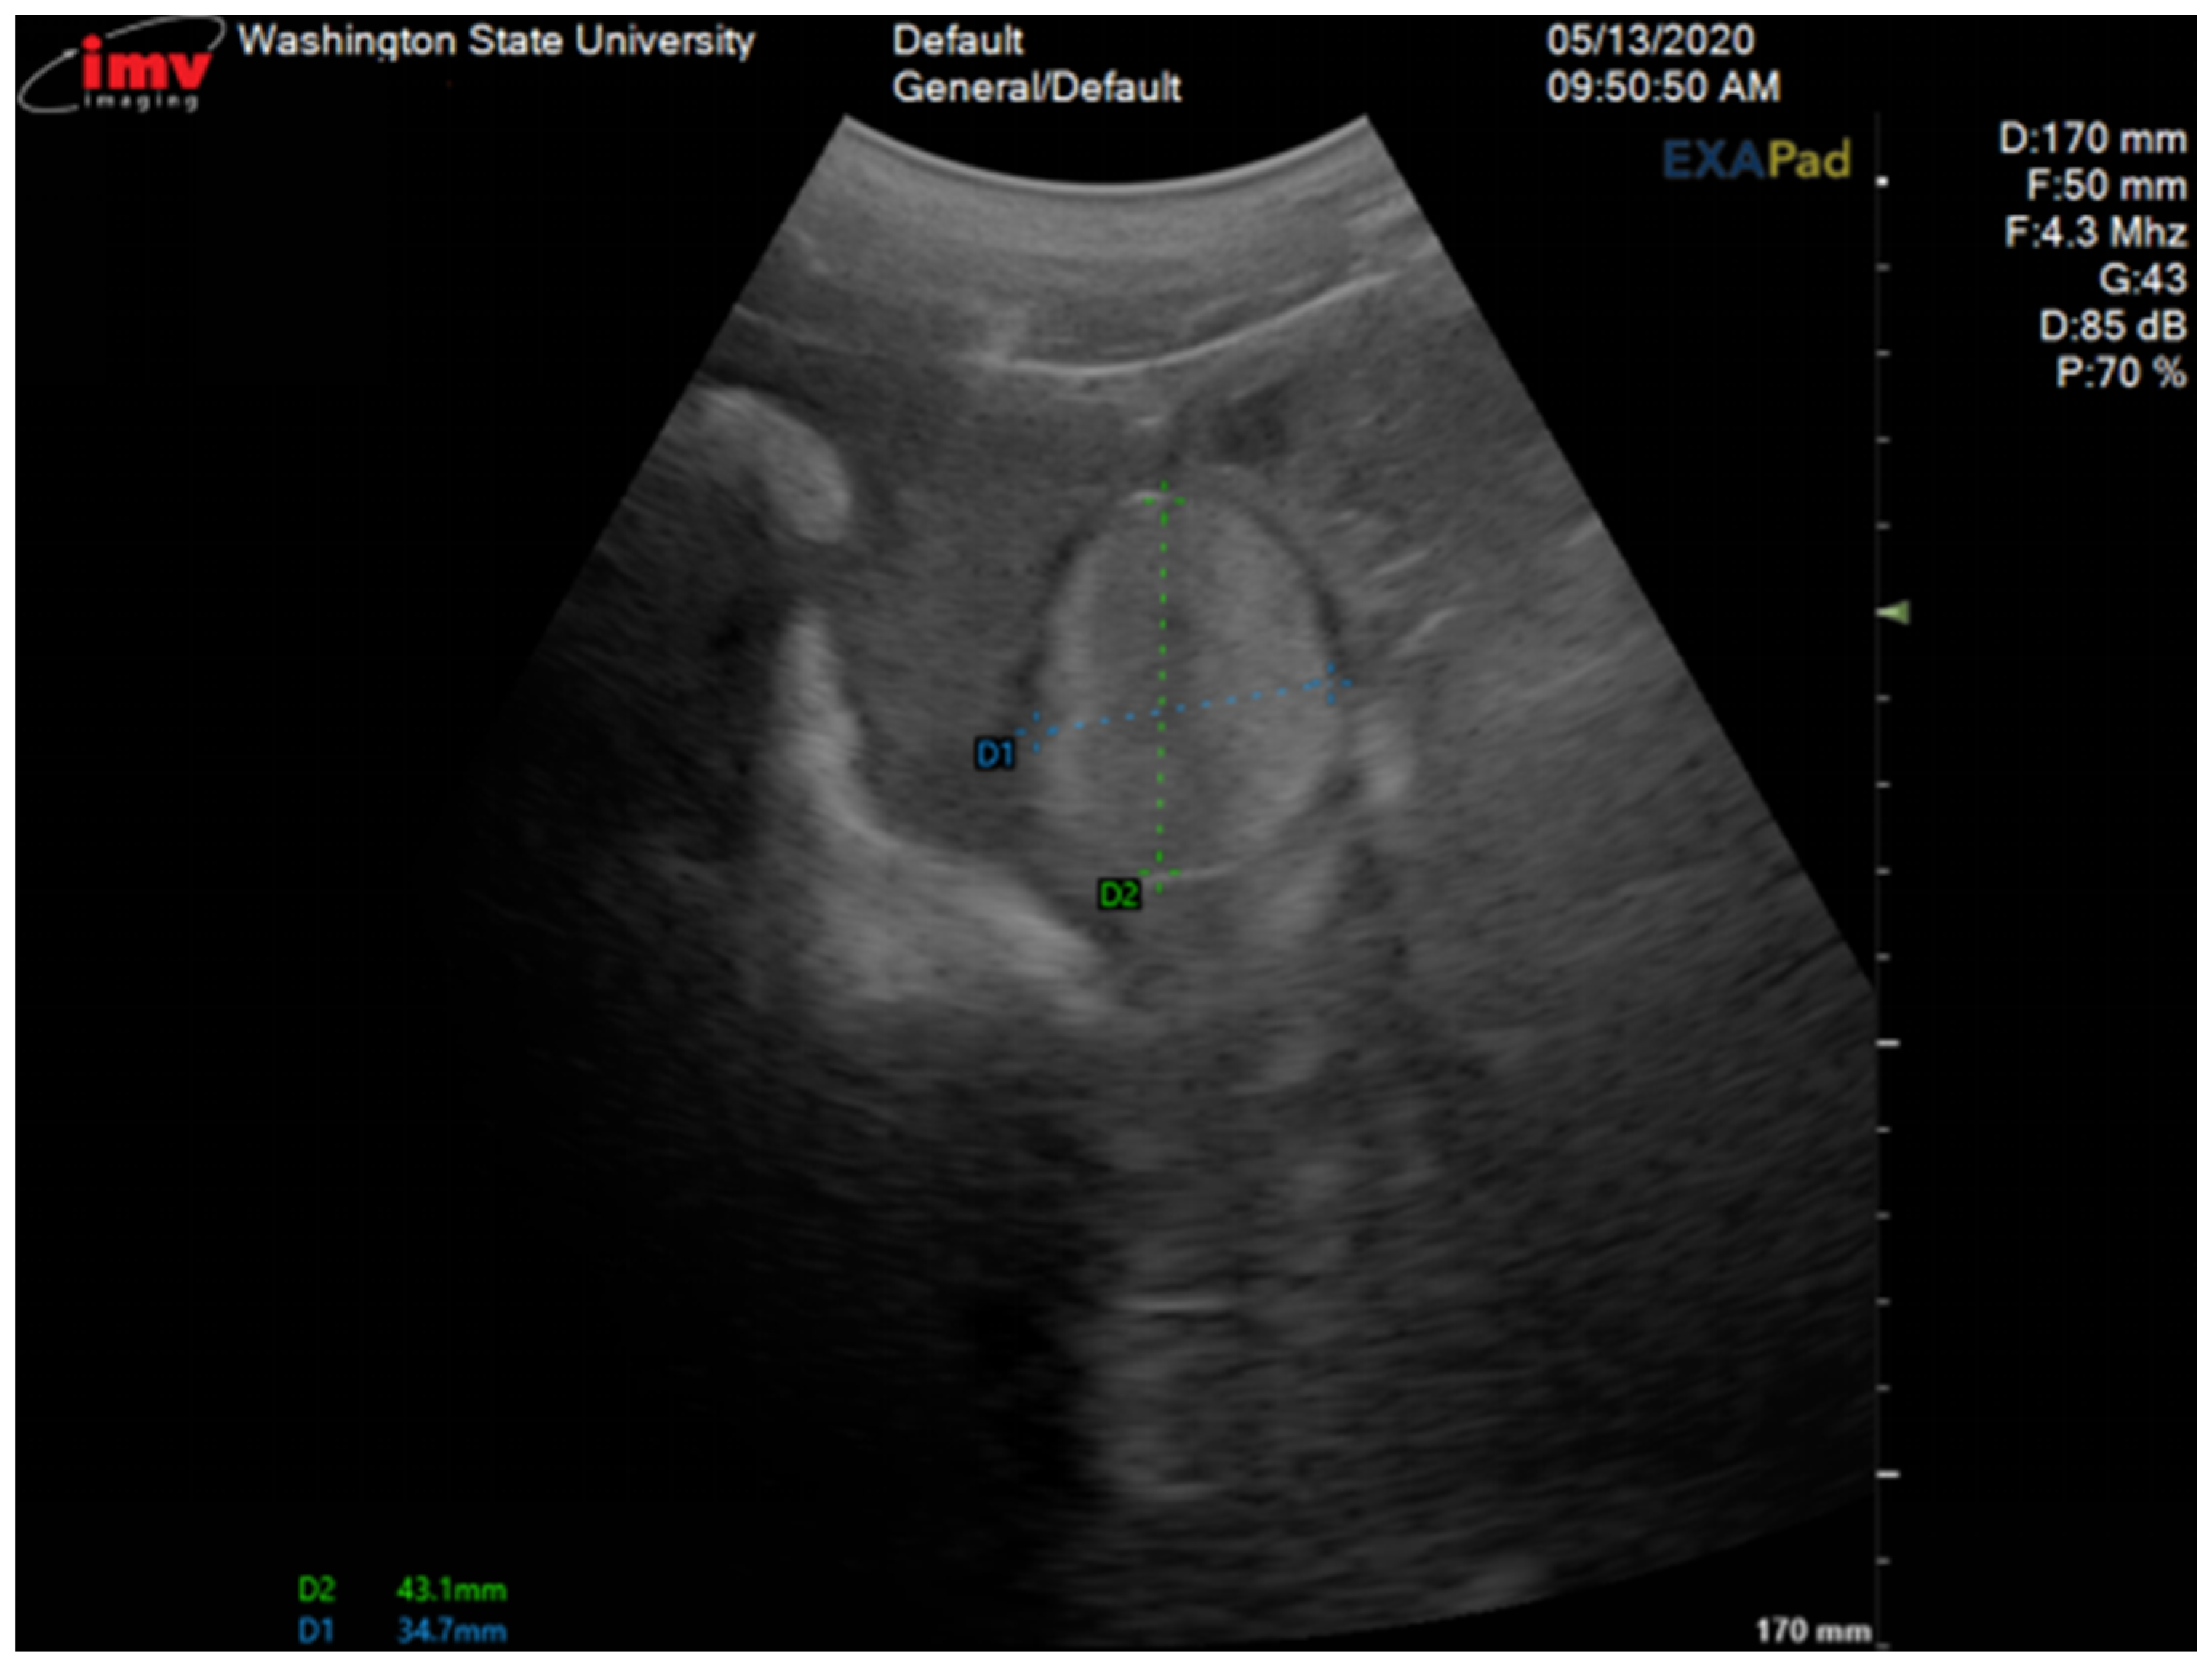

A 2-year-old Large White research gilt was presented to the Comparative Theriogenology service at WSU for infertility. She was produced from the transfer of genetically modified embryos obtained by in vitro fertilization (IVF) that had been treated with CRISPR-Cas9 reagents to mutate the NANOS2 gene. Since birth, the gilt showed a so-called “skyhook” vulva and abnormal estrous cycles. She was artificially inseminated multiple times, starting at 5 months of age, with semen from a proven boar, but never conceived. On transabdominal ultrasonography of the reproductive tract, a unilateral ovotestis was suspected. An exploratory laparotomy was performed and confirmed the presence of ovarian and testicular tissue on her right gonad. The diagnosis was confirmed by histology following unilateral gonadectomy. The cytogenic evaluation revealed the gilt to be XX, 38; SRY-negative. The gilt showed estrus signs 4 months after surgery, and artificial insemination was performed, which resulted in a pregnancy. She delivered six piglets. Necropsy was performed following humane euthanasia. Several abnormalities of the reproductive tract were discovered, including a unilateral mucometra due to a complete septum preventing communication between the right uterine horn and the body of the uterus. This case is novel because it demonstrates that surgical removal is an effective treatment for fertility in SRY-negative XX DSD gilts with partial masculiniza-tion, posing the presence of a normal ovary and a developed oviduct and uterine horn.